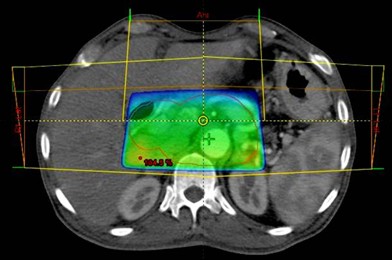

Ten postoperative patients of periampullary cancers were selected for this dosimetric analysis comparing doses to organs at risk using 3D conformal radiotherapy (3DCRT) versus intensity modulated radiotherapy (IMRT). All patients had undergone Whipple’s surgery. Planning CT scans films were taken for the patients with proper immobilization using a multislice CT scanner with slice thickness of 2.5 mm using a multislice CT scanner (GE Healthcare Technologies, Wankesha, WI, USA). The images were transferred to EclipseTM treatment planning system (v.8.6, Varian Associates, Palo Alto, CA, USA). Conturing for treatment volumes was done as per published Radiotherapy and Oncology Group (RTOG) guidelines [7]. The clinical target volume (CTV) included the postoperative tumor bed and draining lymph nodal areas. A 1 cm margin was taken around the CTV to generate the planning target volume (PTV). Critical structures contoured for evaluation included bowel bag, bilateral kidneys, liver, stomach and spinal cord. Two sets of IMRT and 3DCRT plans were generated for each patient. IMRT plans were generated using seven field coplanar beams and 3DCRT planning was done using one anterior and two lateral fields (Figures 1 and 2). A dose of 45 Gy in 25 fractions was prescribed to the planning target volume in both treatment groups. Six MV photons were used for all treatment planning. The plans were optimized to deliver 45 Gy in 25 fractions to the PTV and the optimization was constrained to deliver the prescription dose to greater than 95% of the PTV. Dose volume histograms were generated for all the organs at risk. The dose constraints used for IMRT treatment planning are listed in Table 1. Dosimetric evaluation of doses to organs at risk was done using quantitative analysis of normal tissue effects in clinics (QUANTEC) parameters [8].

Figure 2. Intensity modulated radiotherapy (IMRT) fields for periampullary cancers. |